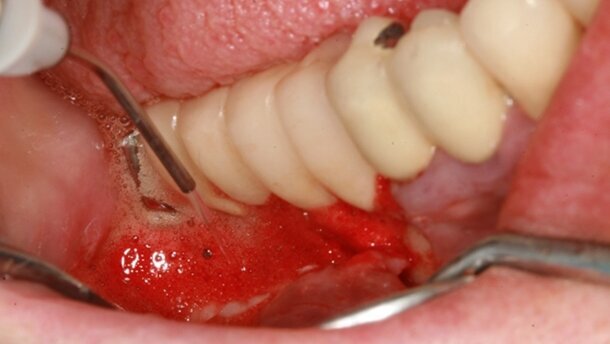

Une fois le lambeau récliné, on objective la quantité de tissu de granulation à éliminer. Le décollement du lambeau est souvent plus compliqué lors des péri-implantites, car on note souvent des adhérences fortes entre la face interne de la muqueuse et le tissu de granulation accroché à la paroi implantaire.

La perte osseuse est horizontale, avec une cratérisation large autour de tous les implants (Fig. 17). L’élimination du tissu infecté se fait à l’aide du laser Er:YAG (Figs. 18–20).

L’élimination du tissu de granulation est plus efficace en orientant la fibre à la jonction entre l’os sain et l’insertion des fibres. Le réglage de la puissance des tirs est dans un 1er temps de 180 mJ, 20 Hz, puis de 200 mJ. Les micro-impacts crées apportent une vascularisation favorable à la cicatrisation osseuse. Cela permet de les enlever en une seule masse, sans disséminer des débris de tissu infecté sur le site.

Puis le réglage est diminué à 100 mJ, 15 Hz, pour éliminer des surfaces implantaires toutes les fibres de granulation accrochées entre les spires, en dirigeant la fibre de 400 μm de l’Er:YAG en direction de la surface implantaire (Figs. 21 et 22).